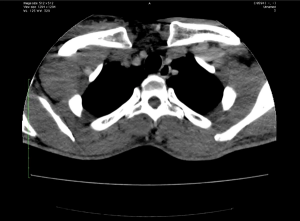

Image IQ Quiz (Video): Patient Presents with Enlarging Neck and Shoulder Region

What is your diagnosis for a patient who presents with increasing size of neck and shoulder region?